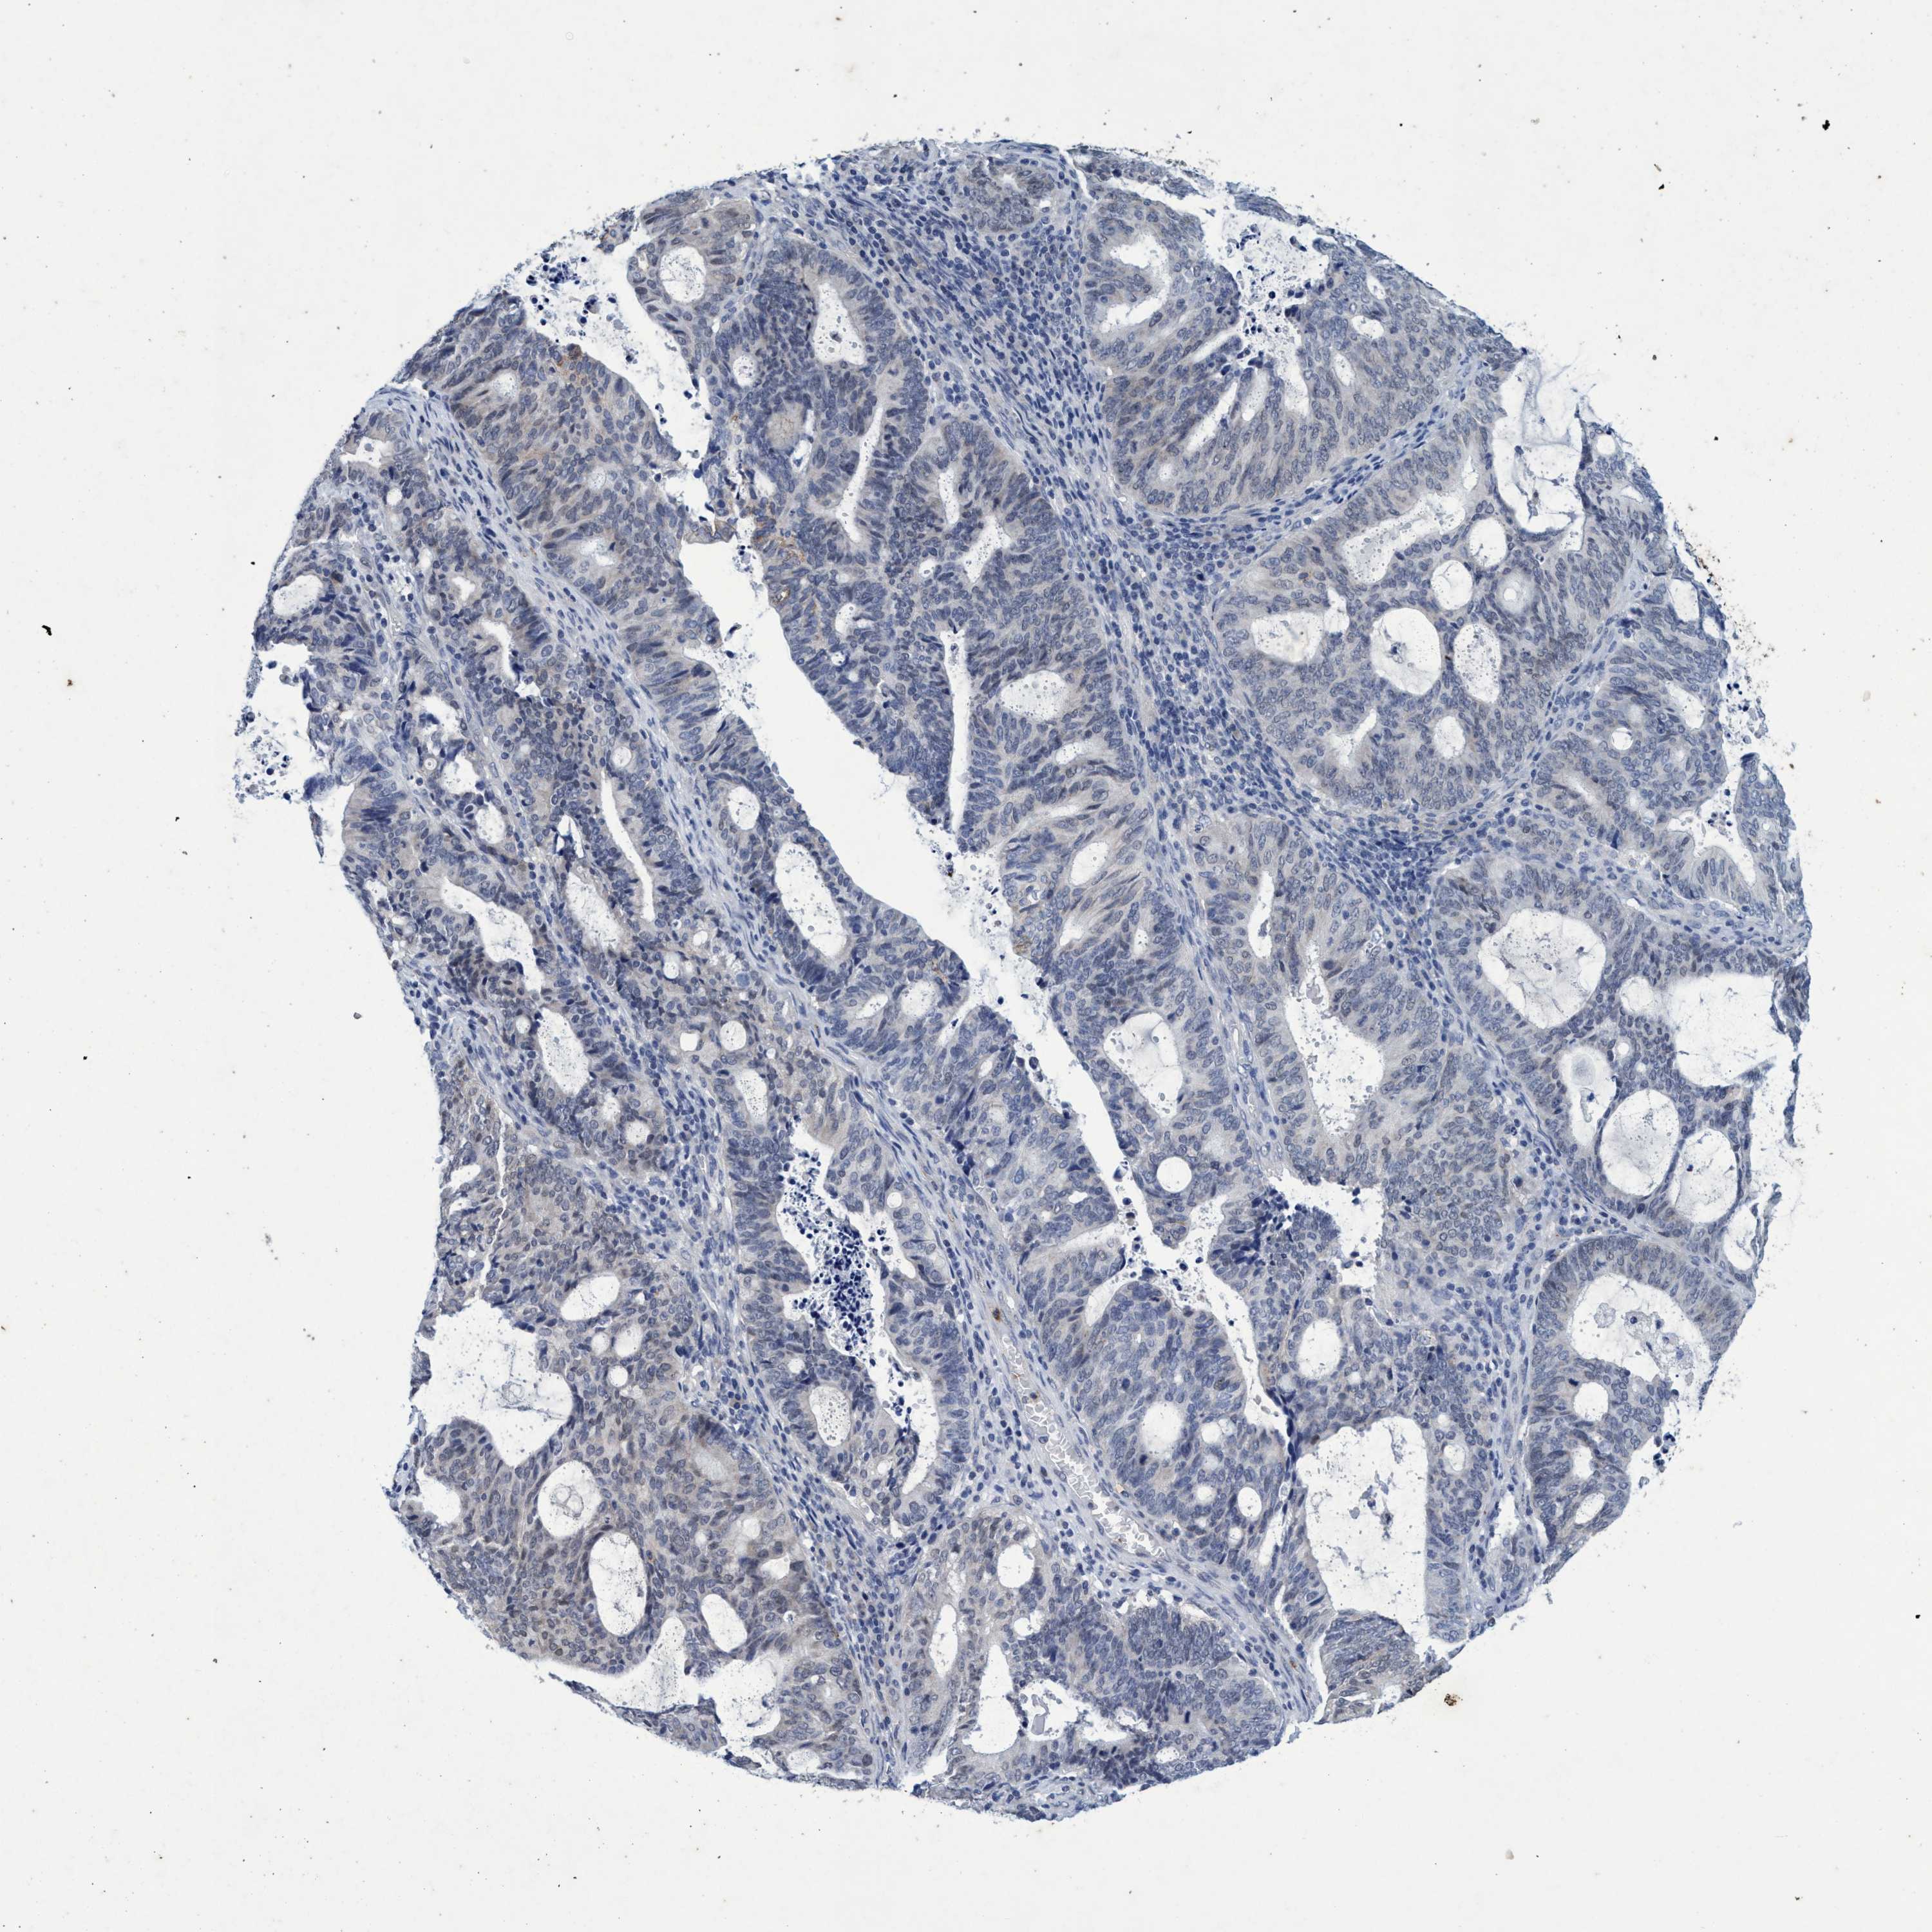

ENDOMETRIAL CANCER - Protein expressioni

A mouse-over function shows sample information and annotation data. Click on an image to view it in a full screen mode. Samples can be filtered based on level of antibody staining by selecting one or several of the following categories: high, medium, low and not detected. The assay and annotation is described here.

Note that samples used for immunohistochemistry by the Human Protein Atlas do not correspond to samples in the TCGA dataset.

Antibody stainingi

Antibody staining in the annotated cell types in the current human tissue is reported as not detected, low, medium, or high, based on conventional immunohistochemistry profiling in selected tissues. This score is based on the combination of the staining intensity and fraction of stained cells.

Each image is clickable and will lead to virtual microscopy that enables deeper exploration of all samples and also displays staining intensity scores, fraction scores and subcellular localization as well as patient and tissue information for each sample.

Antibody HPA035053

Antibody CAB022294

Staining

High

Medium

Low

Not detected

Intensity

Strong

Moderate

Weak

Negative

Quantity

>75%

75%-25%

<25%

None

Location

Nuclear

Cytoplasmic/membranous

Cytoplasmic/membranous,nuclear

Adenocarcinoma, NOS